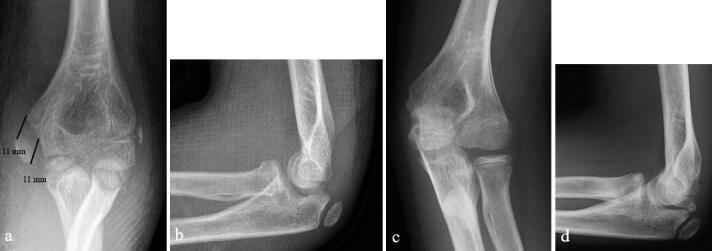

Background and purpose - Controversy exists regarding the optimal treatment for displaced medial epicondyle fractures. We compared the results of nonoperative and operative treatment and calculated the incidence of medial epicondyle fractures in the pediatric census population.Patients and methods - 112 children under 16 years old who sustained > 2 mm displaced fracture of the medial epicondyle were treated in our institution between 2014 and 2019. 80/83 patients with 81 non-incarcerated fractures were available for minimum 1-year follow-up. 41 fractures were treated with immobilization only, 40 by open reduction and internal fixation, according to the preference of the attending surgeon. Outcome was assessed at mean 2.6 years (1-6) from injury with different patient-reported outcome measures. Elbow stability, range of motion, grip strength, and distal sensation were registered in 74/80 patients. Incidence was calculated for 7- to 15-year-olds.Results - Nonoperatively treated children had less pain according to the PedsQL Pediatric Pain Questionnaire (3 vs. 15, p = 0.01) with better cosmetic outcome (VAS 95 vs. 87, p = 0.007). There was no statistically significant difference between the groups in respect of QuickDASH, PedsQL generic core scale, Mayo Elbow Performance Score, grip strength, carrying angle, elbow stability, or range of motion (p > 0.05). All 41 nonoperatively treated children returned to pre-injury sports; of the surgically treated 6/40 had to down-scale their sporting activities. The incidence of displaced (> 2 mm) fractures of the medial epicondyle in children aged 7-15 years was ≥ 3:100,000.Interpretation - Displaced fractures of the medial humeral epicondyle in children heal well with 3-4 weeks' immobilization. Open reduction and screw fixation does not improve outcome.

患者与方法-2014 年至 2019 年,我们机构收治了 112 名 16 岁以下、伴有>2mm 内侧髁突移位骨折的儿童。83 例患者中的 80 例(81 例未嵌顿骨折)获得了至少 1 年的随访。根据主管医生的偏好,41 例采用单纯固定,40 例采用切开复位内固定治疗。采用不同的患者报告结局测量方法评估平均 2.6 年(1-6 年)的结果。在 74/80 例患者中记录了肘部稳定性、活动范围、握力和远端感觉。计算了 7-15 岁儿童的发生率。